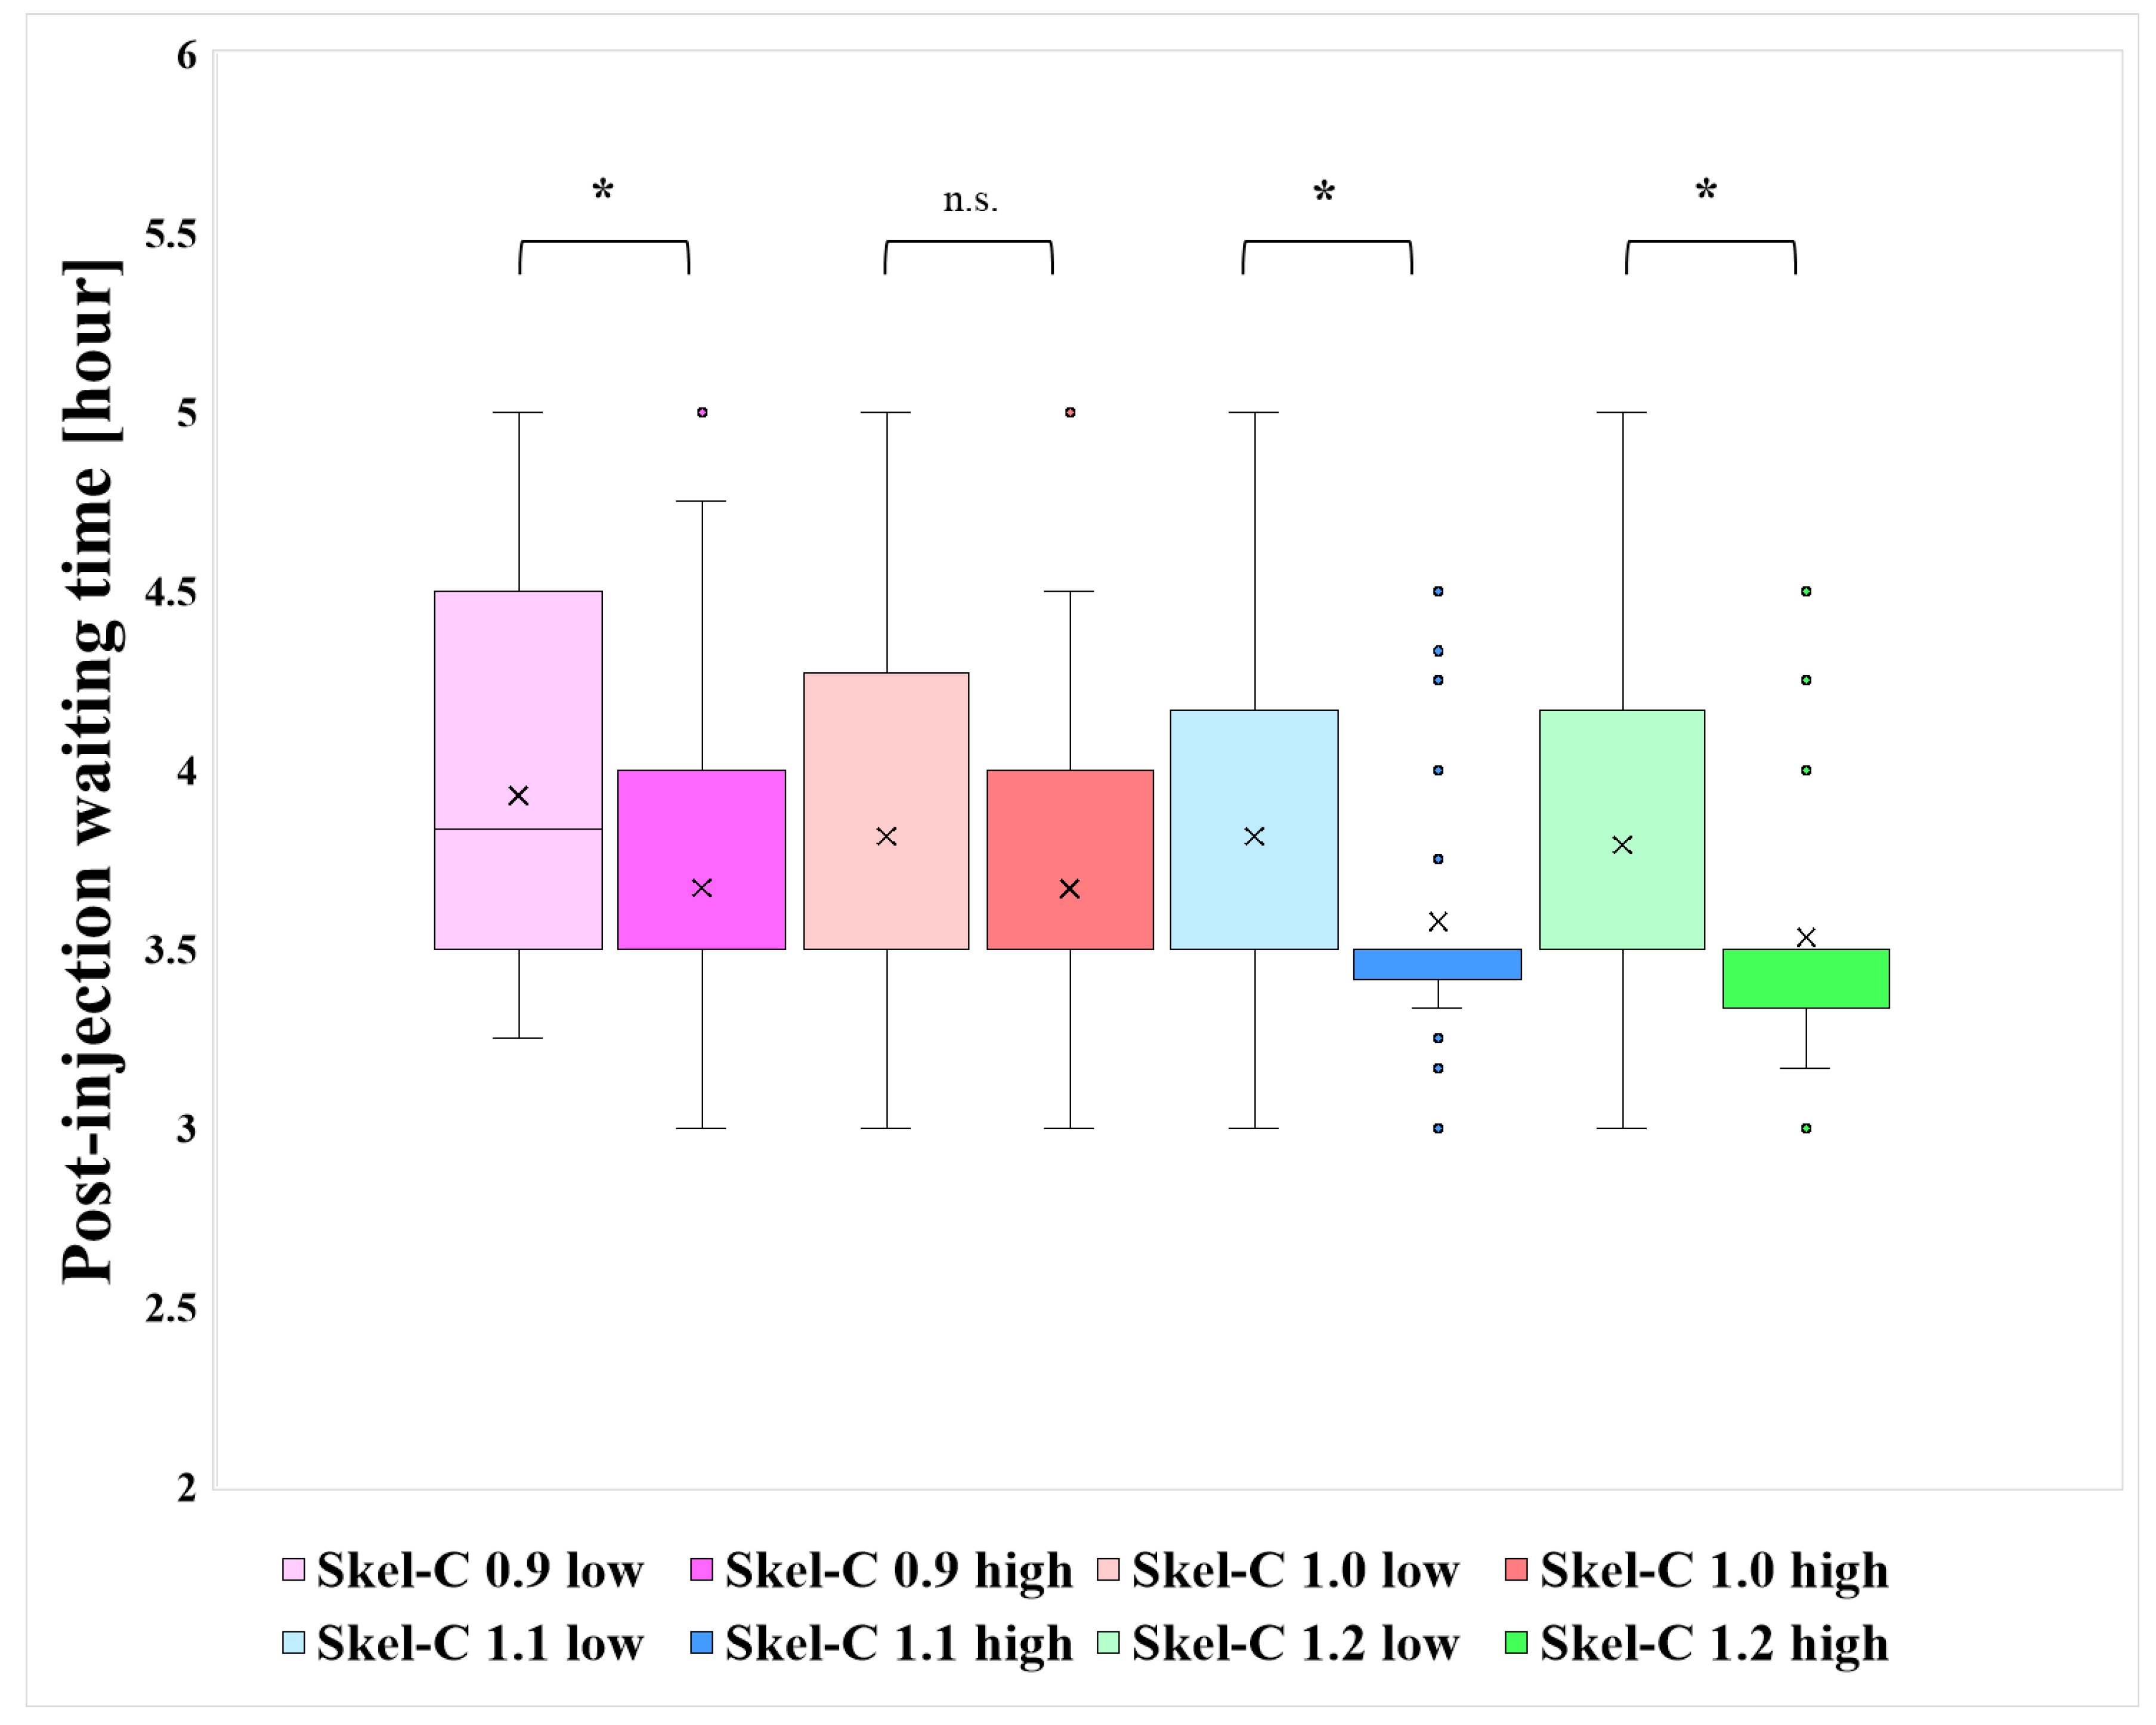

3. Results

4. Discussion

| N | Bone Meta (+) | Bone Meta (−) | Injected Dose [MBq] | Post-Injection Waiting Time [Hour] | |

|---|---|---|---|---|---|

| Skel-C 0.9 low | 42 | 6 | 36 | 755 | 3.93 |

| Skel-C 1.0 low | 87 | 21 | 66 | 757 | 3.83 |

| Skel-C 1.1 low | 137 | 37 | 100 | 752 | 3.84 |

| Skel-C 1.2 low | 167 | 48 | 119 | 753 | 3.82 |

| Skel-C 0.9 high | 194 | 75 | 119 | 751 | 3.73 |

| Skel-C 1.0 high | 149 | 60 | 89 | 749 | 3.72 |

| Skel-C 1.1 high | 99 | 44 | 55 | 751 | 3.66 |

| Skel-C 1.2 high | 69 | 33 | 36 | 747 | 3.63 |